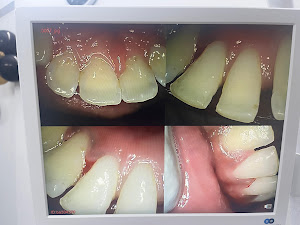

Welcome to our gallery

See how our company transforms ideas into reality. This gallery is a visual testament to our work and achievements.